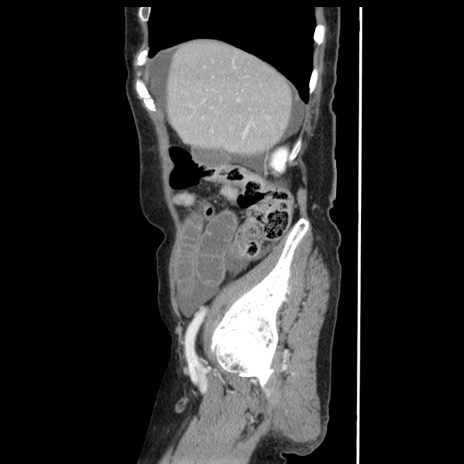

症例1(矢状断像)

【症例】80歳代女性

【主訴】腹痛

【現病歴】8時間前から腹痛あり来院。

【既往歴】糖尿病、脂質異常症、子宮体癌にて子宮全摘術

【身体所見】意識清明・会話良好だが腹痛で苦悶様、全腹部にわたって反跳痛と圧痛あり

【データ】WBC 13600、CRP 0.14、LDH 224、CK 90